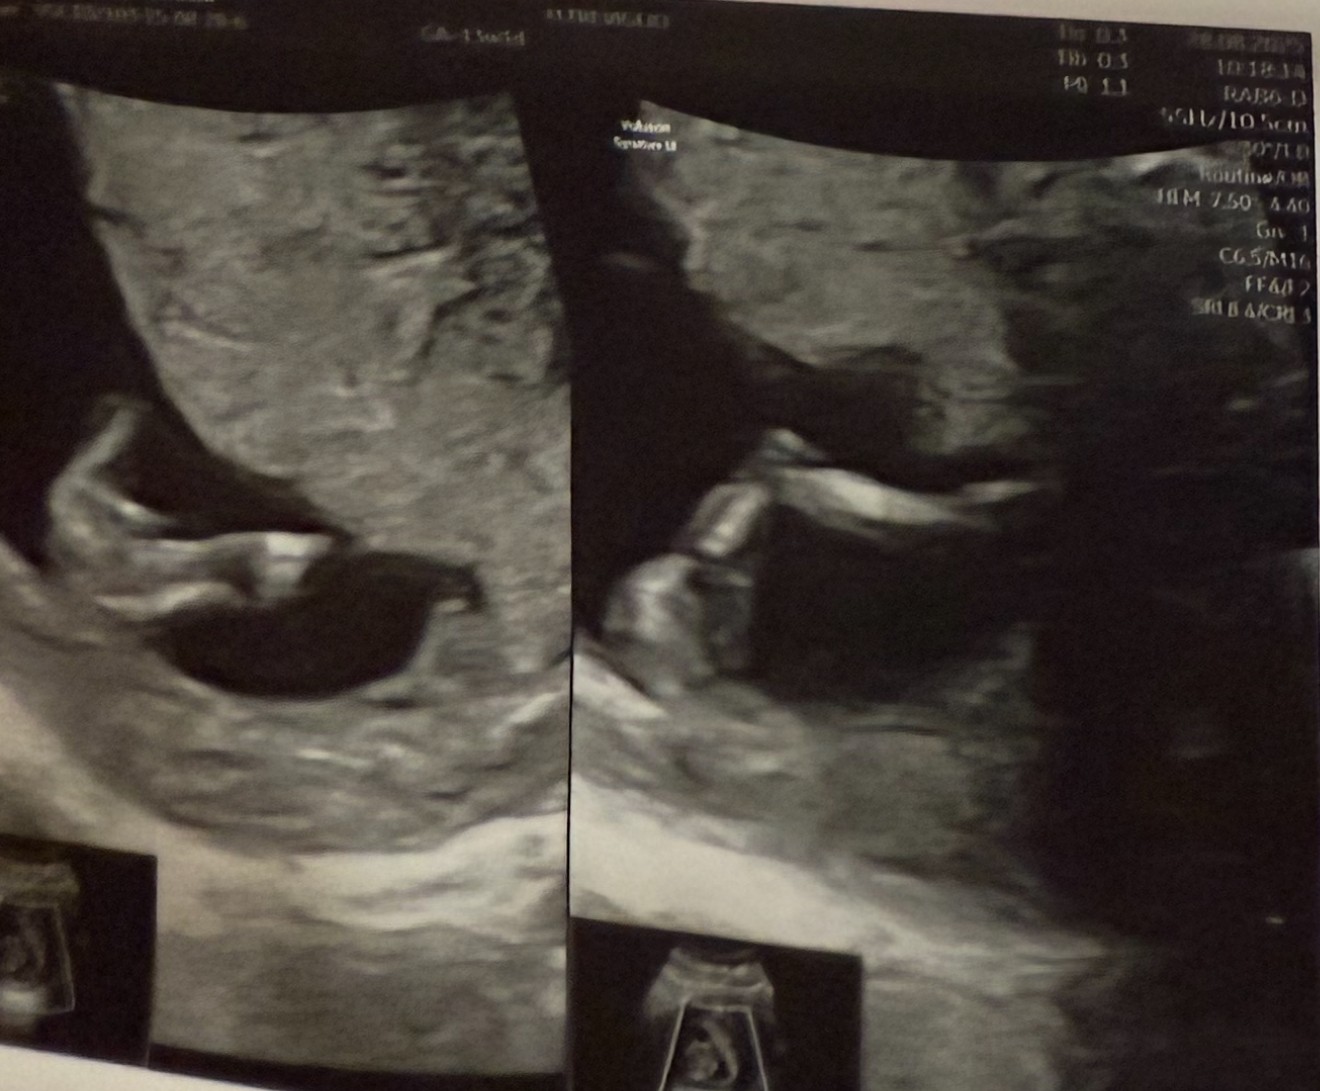

Witam serdecznie czy któraś z was z tego USG potrafi wywnioskować płeć?

Mi się wydaje że coś tam widzę między nogami tam gdzie zaznaczyłam kółeczkiem.

Jeżeli to zdjęcie z 1 prenatalnych, to na tym etapie ciąży nie ma jeszcze nic konkretnego między nogami, jest wyrostek płciowy. Mają go obie płcie.

Jeżeli lekarz nie zaryzykował zgadywanki to zostaje poczekać do prenatalnych w 2 trymestrze.